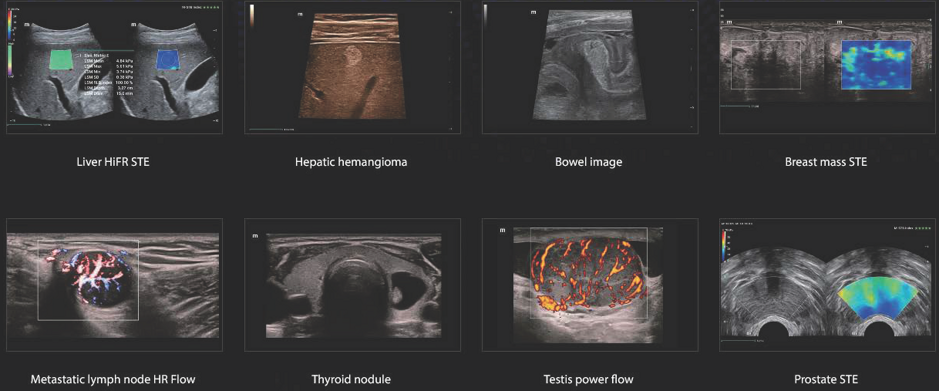

Supersonic "Aixplorer Ultimate, Mach30"

Mindray " Resona , Consona ,Portatili"

Sonoscape

Wisonic

FujiFilm Hitachi Aloka Arietta 650-750-850